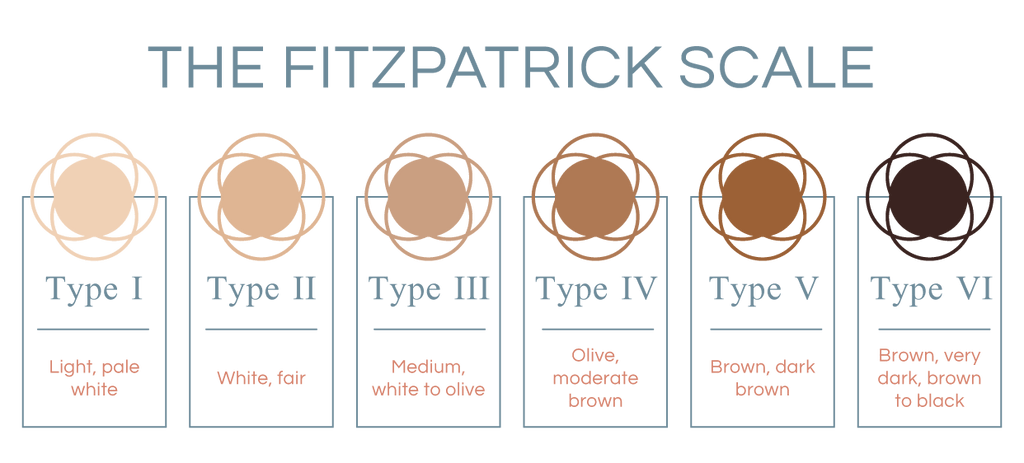

How your skin handles the sun depends on how much melanin you naturally have. The Fitzpatrick scale is a handy guide that classifies skin into six types based on how it reacts to the sun. It’s your skin's superpower.

Your personal reaction to the sun whether you burn, tan, or both depends on the amount of melanin in your skin. Scientists use the Fitzpatrick scale to classify skin into six types based on how it responds to the sun.

Type I: Pale white skin, red or blond hair. This skin always burns and never tans.

Type II: Fair skin, blue or green eyes. This skin burns easily and tans with difficulty.

Type III: Darker white or light brown skin. This skin sometimes burns but gradually tans.

Type IV: Light brown or olive skin. This skin burns minimally and tans easily.

Type V: Brown skin. This skin rarely burns and tans very easily and darkly.

Type VI: Dark brown or black skin. This skin never burns and always tans darkly.

No matter your skin type, UV radiation can still cause long-term damage like premature aging and an increased risk of skin cancer. Even if you tan easily, that tan is still a sign of damage. That's why protecting your skin is so important, regardless of your complexion!